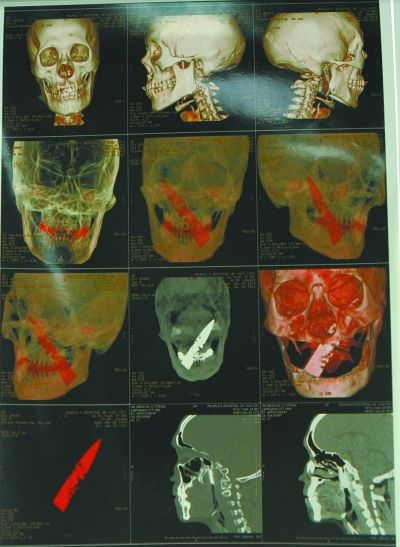

2月12日上午8點(diǎn)30分到下午12點(diǎn)30分,玉溪市人民醫(yī)院手術(shù)室里,經(jīng)過4個(gè)小時(shí)緊張手術(shù),醫(yī)生成功將滯留在李福頭里的一把長(zhǎng)10cm、寬1.8cm、厚0.24cm的斷刀取出。據(jù)了解,這把長(zhǎng)達(dá)10cm的斷刀由他的右下頜處插入,依次穿過他的舌根、鼻咽、肌肉,最后尖端插在了腦上。

玉溪市人民醫(yī)院口腔科副主任醫(yī)師徐穩(wěn)說,當(dāng)時(shí)自己在門診接診了由元江縣醫(yī)院的醫(yī)生帶來的患者李福,當(dāng)時(shí)從元江縣醫(yī)院所照的X片上可以看出患者顱內(nèi)有一很清楚的金屬物體,但當(dāng)時(shí)還不知道是什么物體。后來又對(duì)病人進(jìn)行了更為準(zhǔn)確的CT和血管成像檢查,確定了患者顱內(nèi)的是一把長(zhǎng)達(dá)10cm的斷刀。顱內(nèi)有這么長(zhǎng)的異物,患者還能吸煙、甚至吸水煙筒,徐醫(yī)生表示自己很吃驚。

據(jù)神經(jīng)外科羅志偉醫(yī)生介紹,針或者釘?shù)任矬w插入人的大腦,人還能存活都是可以理解的,而如此長(zhǎng)的斷刀進(jìn)入患者的顱內(nèi),患者還能存活,且時(shí)間長(zhǎng)達(dá)4年多,實(shí)在是一個(gè)很大的奇跡。這把斷刀從舌根部插入,傾斜向上,經(jīng)過鼻、咽、肌肉直至左腦,人的面部有很多神經(jīng),刀在進(jìn)入頭部時(shí)避開了腦動(dòng)脈以及一些重要的面部神經(jīng),沒有導(dǎo)致面癱或者大出血等嚴(yán)重后果。羅志偉醫(yī)生說,這是自己從醫(yī)近30年以來都沒有見過的,毫厘之差使得患者幸運(yùn)地保住了性命,這也算是患者不幸中的大幸。

金屬異物位于頸部大血管前方,離腦動(dòng)脈約3.5mm。尖端刺入顱內(nèi)左側(cè)顳葉腦組織底部約1.3cm,周圍輕度水腫和炎癥改變;顱底部分即刀尖部的異物主體位于圓孔和卵圓孔之間,緊鄰三叉神經(jīng)、上頜動(dòng)脈、面動(dòng)脈,進(jìn)行手術(shù)存在很大的難度。玉溪市人民醫(yī)院在此之前還未遇到過如此特殊的病例,斷刀在患者顱內(nèi)長(zhǎng)達(dá)4年多,患者都能進(jìn)行正常生活和勞作,而且基本不受影響,甚至可飲酒、吸煙筒。而這個(gè)手術(shù)存在很大的風(fēng)險(xiǎn),一旦手術(shù)發(fā)生意外,后果不堪設(shè)想,但是在得知顱內(nèi)存有金屬異物后李福已出現(xiàn)焦慮、憤怒等反應(yīng),手術(shù)意愿強(qiáng)烈。

2月13日上午9點(diǎn),手術(shù)結(jié)束的第二天,記者來到了玉溪市人民醫(yī)院神經(jīng)外科辦公室,神經(jīng)外科主任羅志偉在電腦上向記者展示了當(dāng)時(shí)所照的片子,以及從李福顱內(nèi)取出的斷刀,斷刀兩端仍然完好,中間部分已經(jīng)被腐蝕。羅主任說,當(dāng)時(shí)自己即便在隔著近半米的距離對(duì)取出的斷刀進(jìn)行清理時(shí),也能聞到很濃烈的臭味。